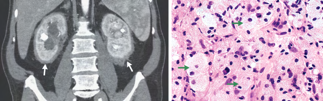

Recent studies indicate that Generative Pre-trained Transformer 4 with Vision (GPT-4V) outperforms human physicians in medical challenge tasks. However, these evaluations primarily focused on the accuracy of multi-choice questions alone. Our study extends the current scope by conducting a comprehensive analysis of GPT-4V's rationales of image comprehension, recall of medical knowledge, and step-by-step multimodal reasoning when solving New England Journal of Medicine (NEJM) Image Challenges - an imaging quiz designed to test the knowledge and diagnostic capabilities of medical professionals. Evaluation results confirmed that GPT-4V outperforms human physicians regarding multi-choice accuracy (88.0% vs. 77.0%, p=0.034). GPT-4V also performs well in cases where physicians incorrectly answer, with over 80% accuracy. However, we discovered that GPT-4V frequently presents flawed rationales in cases where it makes the correct final choices (27.3%), most prominent in image comprehension (21.6%). Regardless of GPT-4V's high accuracy in multi-choice questions, our findings emphasize the necessity for further in-depth evaluations of its rationales before integrating such models into clinical workflows.